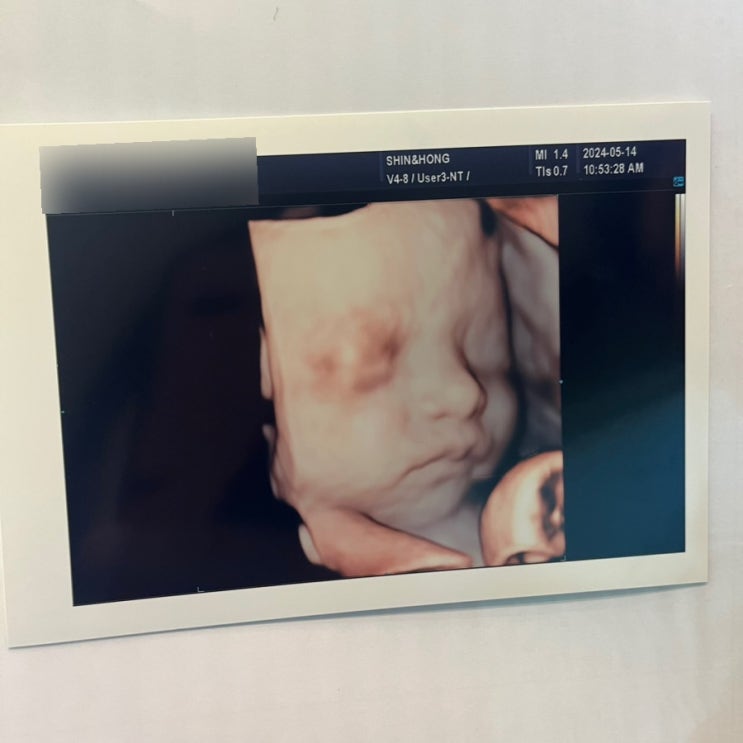

28 - 30주 : 입체초음파, 분만병원 전원, 용용룸, 식단관리(?)

입체초음파 기다리고 기다리던 입체초음파날!! 입체초음파를 자주 봐주는 병원도 있던데 요기는 입체초음파...